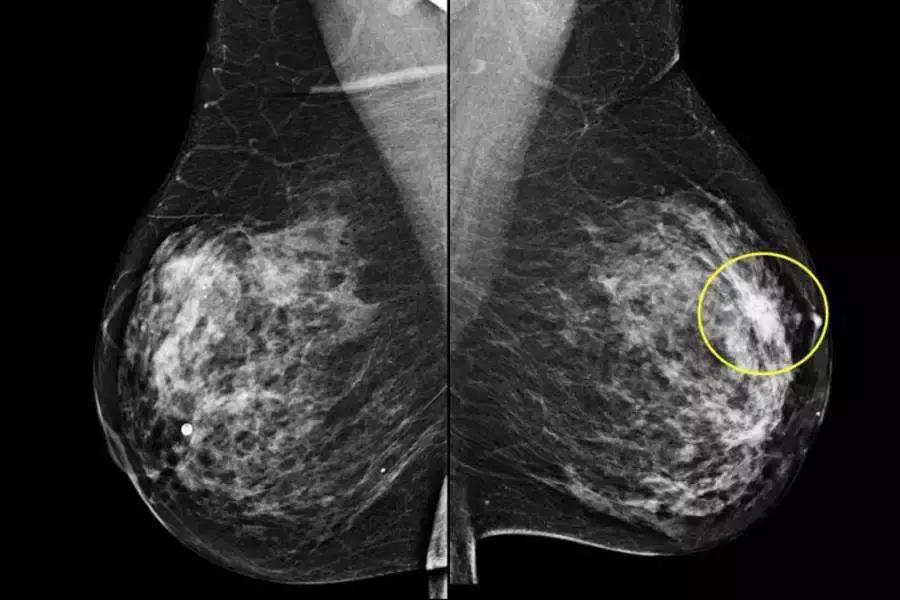

辅助检查是进一步明确诊断的手段,主要包括彩色超声检查,乳腺X线钼靶摄片和选择性乳腺导管造影X线检查,对有乳头溢液者还可选择进行纤维乳管镜检查。

对可疑病灶进行病理学穿刺活检排除乳腺癌。对乳腺增生症病理形态学诊断仍然是临床诊断的金标准。

需要指出的是,对于40岁以上的女性患者,特别是有乳房局限性增厚或肿块样改变者,不能轻易诊断为乳腺增生症,需要进行上述检查排除乳腺癌之后方可诊断为乳腺增生症。